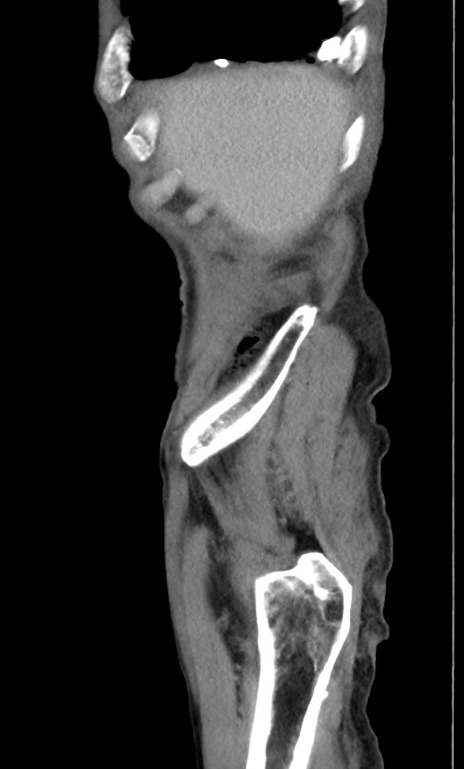

冠状断像

【症例】 70歳代男性

【主訴】右鼠径部腫瘤、疼痛

【既往歴】膀胱癌にて膀胱全摘、両側尿管皮膚瘻